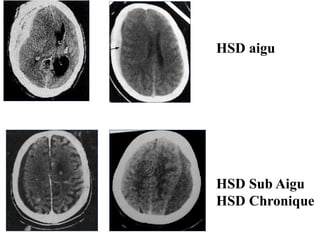

HSD aigu

HSD Sub Aigu

HSD Chronique

• TDM : Stadede début: formation spontanément hyperdense en croissant Stade sub Aigu: aspect isodense Stade chronique: hypodense (plusieurs semaines après le traumatisme ) Recherche de signes d’engagement .

HSD aigu HSD SubAigu HSD Chronique